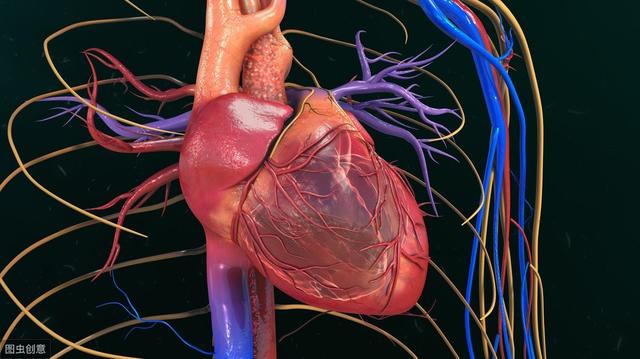

在日常生活中,很多人发生过深呼吸时左胸痛的情况,非常难受,往往还不知道原因。通常疼痛一会过后,就会慢慢缓和过来。有些人认为是心肌炎,平时又没有痛过,就不会特别关注。但是深呼吸左胸痛也有可能与心肌梗塞有关,一定要引起足够的重视。

深呼吸左胸痛的原因

1、过于疲劳引起左胸口疼痛。这种原因的患者平时身体健康,只是由于最近工作或生活过于劳累,才会引起胸口疼痛。

2、心肌炎引起左胸口疼痛,主要表现为左胸口疼痛,会伴有多汗、发热、咽痛、咳嗽、呕吐、腹泻、肌肉酸痛、心律失常等症状。如果患有心肌炎,不必过于紧张,多发于办公室白领,可治愈。

3、焦虑引起胸口疼痛。由于生活中过于焦虑,就会出现胸口痛的情况,同时会伴有头晕、恶心、手脚发麻等症状。

4、冠心病引发心绞痛,通常表现是左胸压榨痛、闷痛、隐痛等,疼痛会向后背、左臂内侧、牙齿等地方扩散,持续时间时长时短,通常不会超过30分钟。如果疼痛加剧超过半个小时,就要警惕急性心梗,务必及时就医。